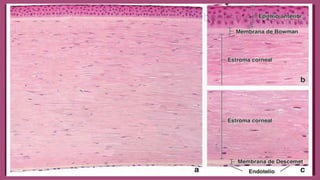

CÓRNEA

○ Epitelio corneal

■ Epitelio plano estratificado sin estrato córneo

○ Membrana de Bowman

○ Estroma corneal

○ Membrana de Descement

○ Endotelio corneal

Bembrana de Bowman

○ Bembrana basal anterior

○ Entre el epitelio corneal y

estroma corneal

○ Barrera contra la

diseminación de

infecciones

○ No se regenera

○ Constituida por fibras de

colágeno V, VI, III, I

○ Sustancia propia

○ Formada por laminillas,

que consta de haces

paralelas de fibrillas de

colágeno (I, III, V y VI)

Bembrana de Descemet

○ Bembrana basal posterior

○ Separa el endotelio corneal

de la estroma corneal

contigua.

○ Se regenera con rapidez

○ Se engruesa con la edad

Endotelio Corneal

○ Capa simple de células

aplanadas que tapiza la

superficie de la córnea que

limita la cámara anterior.

○ Intercambio metabólico